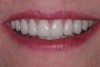

(7.) “Ditching” from GERD around existing restorations may be noted upon examination.

Figure 7

A common form of gastric erosion results from regurgitation. It presents with prominent involvement of the maxillary anterior lingual surfaces (Figure 6). Erosion starts at the gingival margin and reaches to the incisal edge. Gastric reflux disease (or “GERD”) can also cause erosion, mostly on the mandibular posterior teeth. Ditching around existing restorations may also be noted upon examination (Figure 7). A habitual pattern of “Coke swishing” may also produce varied areas of erosion.5